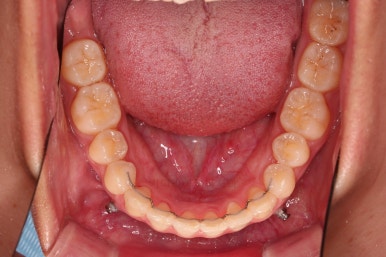

아랫니는 앞니가 더이상 뒤로 들어가지 않도록 어금니를 앞으로 당기는 셋팅을 해줍니다.

그래서 위아래 좌우 모두 다른 용도로 미니스크류가 식립되었고요.

각각의 방향으로 계속 당겨줍니다.

아래는 아직 틈이 많이 보이죠.

어금니를 부산치아교정 통해 계속 앞으로 당겨줍니다.

아랫니 틈은 거의 없어졌네요.